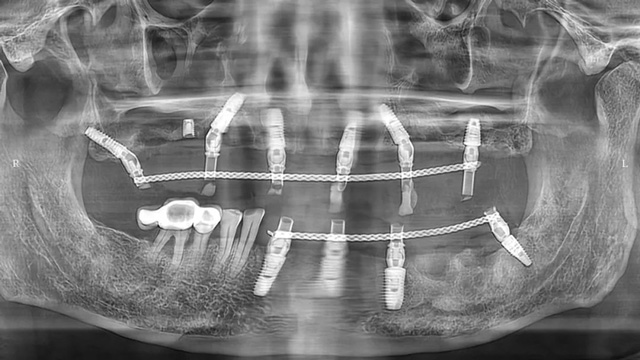

“我们通过上半口即拔即种、即刻修复治疗,将他上面残留的种植体拆除,同时拔掉无法保留的牙齿,手术同期埋入6颗种植体,术后佩戴了临时牙冠。由于骨量不好,有3颗种植体采用倾斜植入,1颗做了上颌窦提升植入。”

上半口即刻种植后全景片

两周后吴叔叔回院拆线,完成了下牙的多颗种植治疗。别看下面的种植数量少,难度却并不低。据余国庆医生介绍,有一颗种植体采用的是倾斜植入,因为之前的种植体周围有感染,拆除种植体后只能在旁边一个极其有限的范围内种植,种植窝洞的位置需要非常精准,很考验医生的技术和经验。

下颌即刻种植后全景片